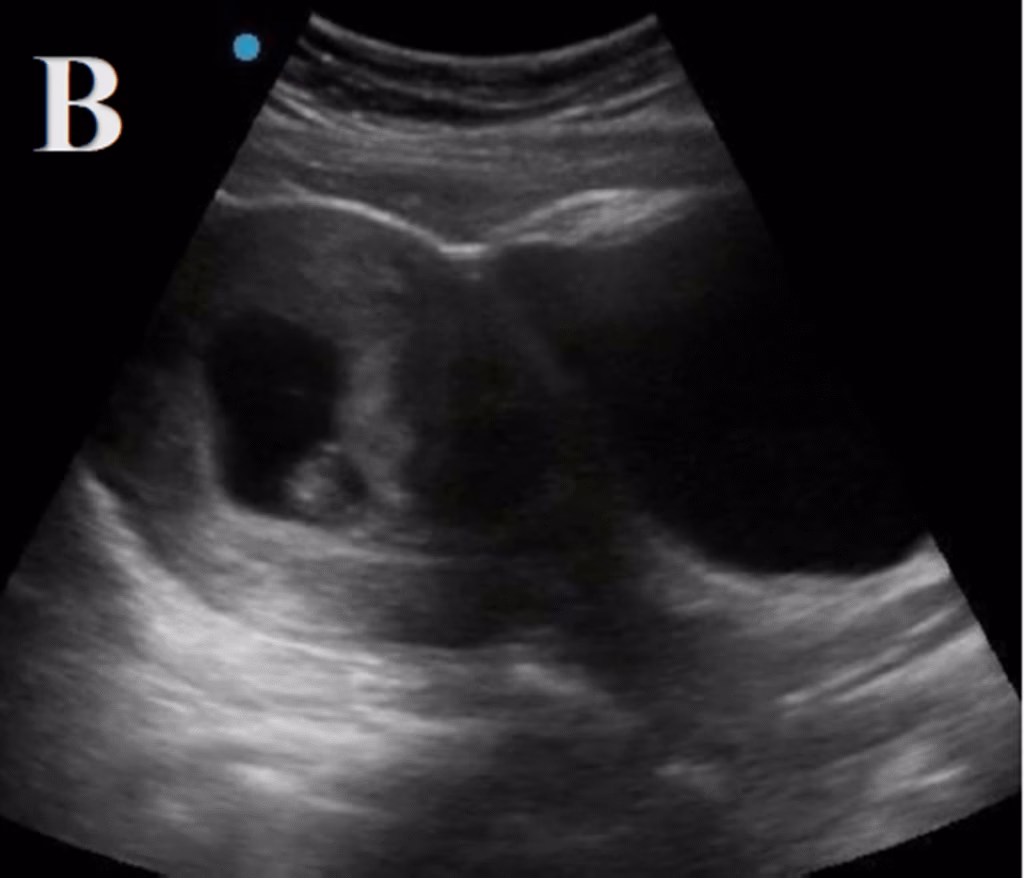

#5 [P]regnancy: Is there an intrauterine pregnancy? Yes or no. A yolk sac (+/- a fetal pole) in a gestational sac and myometrial mantle >8 mm supports the presence of an intrauterine pregnancy. This effectively rules out an ectopic pregnancy, except in exceedingly rare circumstances such as, but not limited to, heterotopic pregnancies.

The focused question for the first trimester POCUS is whether there is an intrauterine pregnancy present. An intrauterine pregnancy is defined as a gestational sac containing a yolk sac within the endometrium in two planes [33] (Figure 7). It is important to ensure that at least 8 mm of endometrium is surrounding the gestational sac so as to not miss an interstitial ectopic pregnancy. This measurement is termed the “myometrial mantle.” A gestational sac alone is not sufficient to determine an intrauterine pregnancy. An estimated10-20% of ectopic pregnancies have a pseudo-gestational sac [33]. A visualized intrauterine pregnancy on POCUS effectively rules out ectopic pregnancy, excluding specific circumstances such as in-vitro fertilization in which the likelihood of a heterotopic pregnancy significantly increases. The pooled sensitivity of emergency physician-performed evaluation for intrauterine pregnancy is 99.3% (95% CI: 96.6-100%) [27]. This data comes from studies that included both transvaginal and transabdominal pelvic POCUS examinations, so if there is concern for ectopic pregnancy and no intrauterine pregnancy is seen on transabdominal POCUS, the patient requires a transvaginal ultrasound to further evaluate.

Figure 7. Point of care ultrasound (POCUS) demonstrating an intrauterine pregnancy (a gestational sac containing a yolk sac within the endometrium in 2 planes) with measurement of the myometrial mantle.

Transabdominal Scanning Technique: The preferred transducer to evaluate for an intrauterine pregnancy via the transabdominal approach is the 3.5-5 MHz curvilinear transducer. The patient should be in supine position. The transabdominal assessment is best obtained with a full urinary bladder, which is an acoustic window to identify the uterus. An inadequately filled bladder is one of the most common reasons for a technically inadequate transabdominal examination. The uterus is a globe-shaped structure, so at least two views are necessary for complete evaluation of the uterus: transabdominal and longitudinal views. To begin, the transducer should be placed over the pubic symphysis with the indicator pointed to the patient’s right to obtain the transverse view of the uterus. Next, fan all the way through by angling the transducer towards the head and moving downward towards the feet. To obtain the sagittal plane, rotate the transducer towards the operator’s right-side, with the indicator pointing to the patient’s head, then fan left to right to fan through and obtain images.

Transvaginal Scanning Technique: The preferred transducer to evaluate for an intrauterine pregnancy via the transvaginal approach is the high-frequency intracavitary transducer (ranging from 5-9 MHz). After performing the transabdominal ultrasound, the patient should empty their bladder. The patient should be supine in a lithotomy position. Using a sterile transducer, the transducer tip should be covered with gel, then  a sterile cover should be placed over the transducer with a small amount of sterile conducting gel. Two views are necessary for complete evaluation of the uterus: one transverse view and one longitudinal view, both demonstrating the endometrial stripe and uterine contents, if present. With the transducer held with the indicator pointed toward the ceiling, the transducer should be inserted into the vaginal canal. In the sagittal plane, the transducer should be moved side to side, fanning through the entire body of the uterus. Angling the transducer handle toward the ceiling will bring the cervix into view (angling the tip toward the posterior fornix of the vaginal canal). Next, the transducer should be rotated toward the patient’s right to obtain the transverse view. Fanning the transducer up and down will show anterior to posterior views of the uterus. From this point, the fallopian tubes can be followed to visualize the ovaries. If the iliac vessels can be observed, the ovaries should be anterior and medial to the vessels. The ovaries can be identified by the multiple follicles.